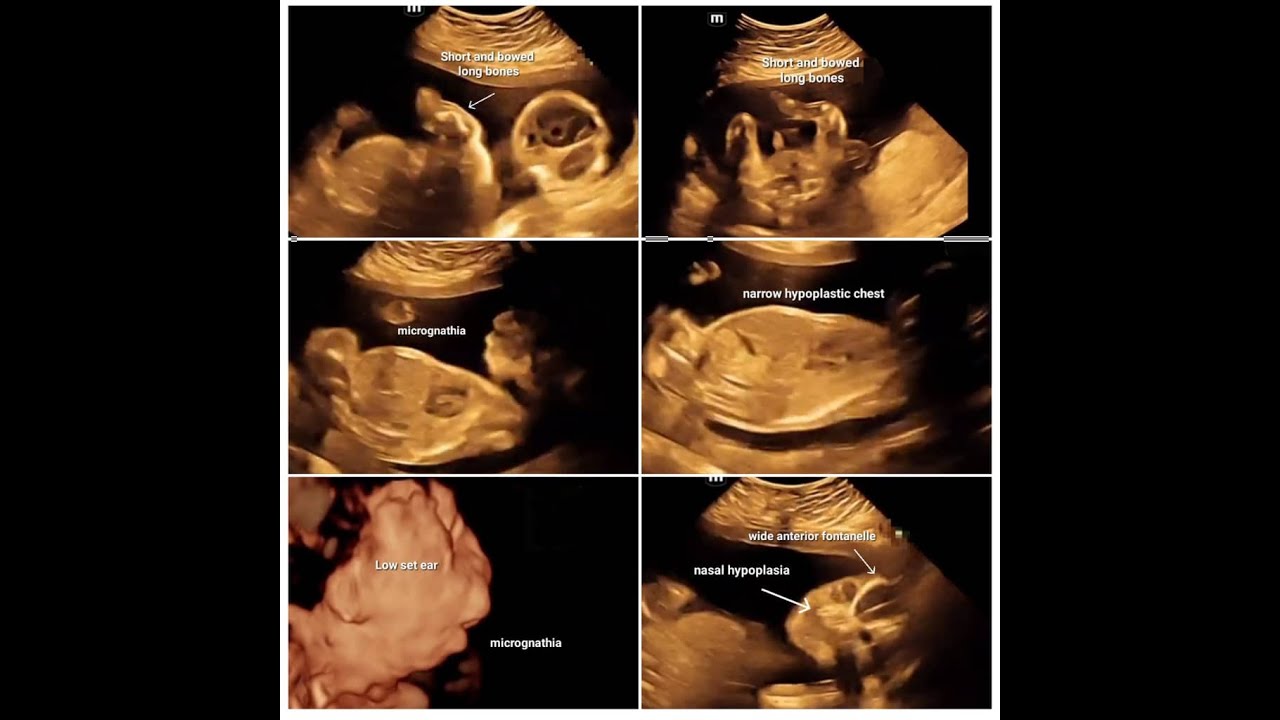

Скачать или смотреть asphyxiating skeletal dysplasia fetal ultrasound for DD ? campomelic dysplasia

asphyxiating skeletal dysplasia fetal ultrasound  for DD ? campomelic dysplasia

Ob&gyn ultrasound diploma / fetal ultrasound diploma / fetal medicine diploma